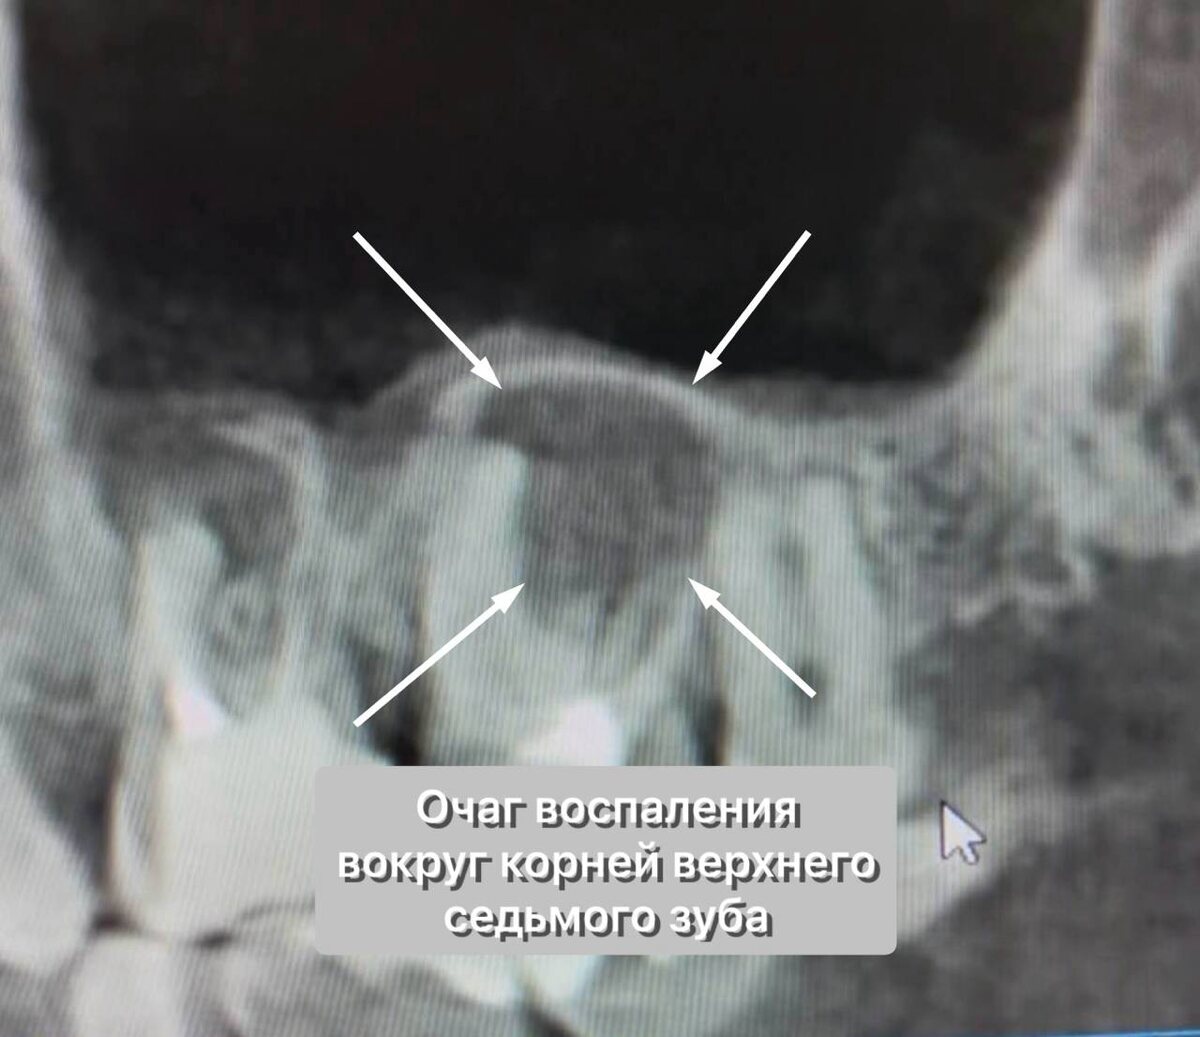

Но на КТ вскрылась правда:

КТ 2.7 зуба - периодонтит

Обширные очаги воспаления в области корней обоих зубов. Гайморова пазуха очень близко, но на момент выполнения рентгенограммы полость её чистая, без содержимого.